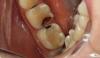

Фотоотчет работы.